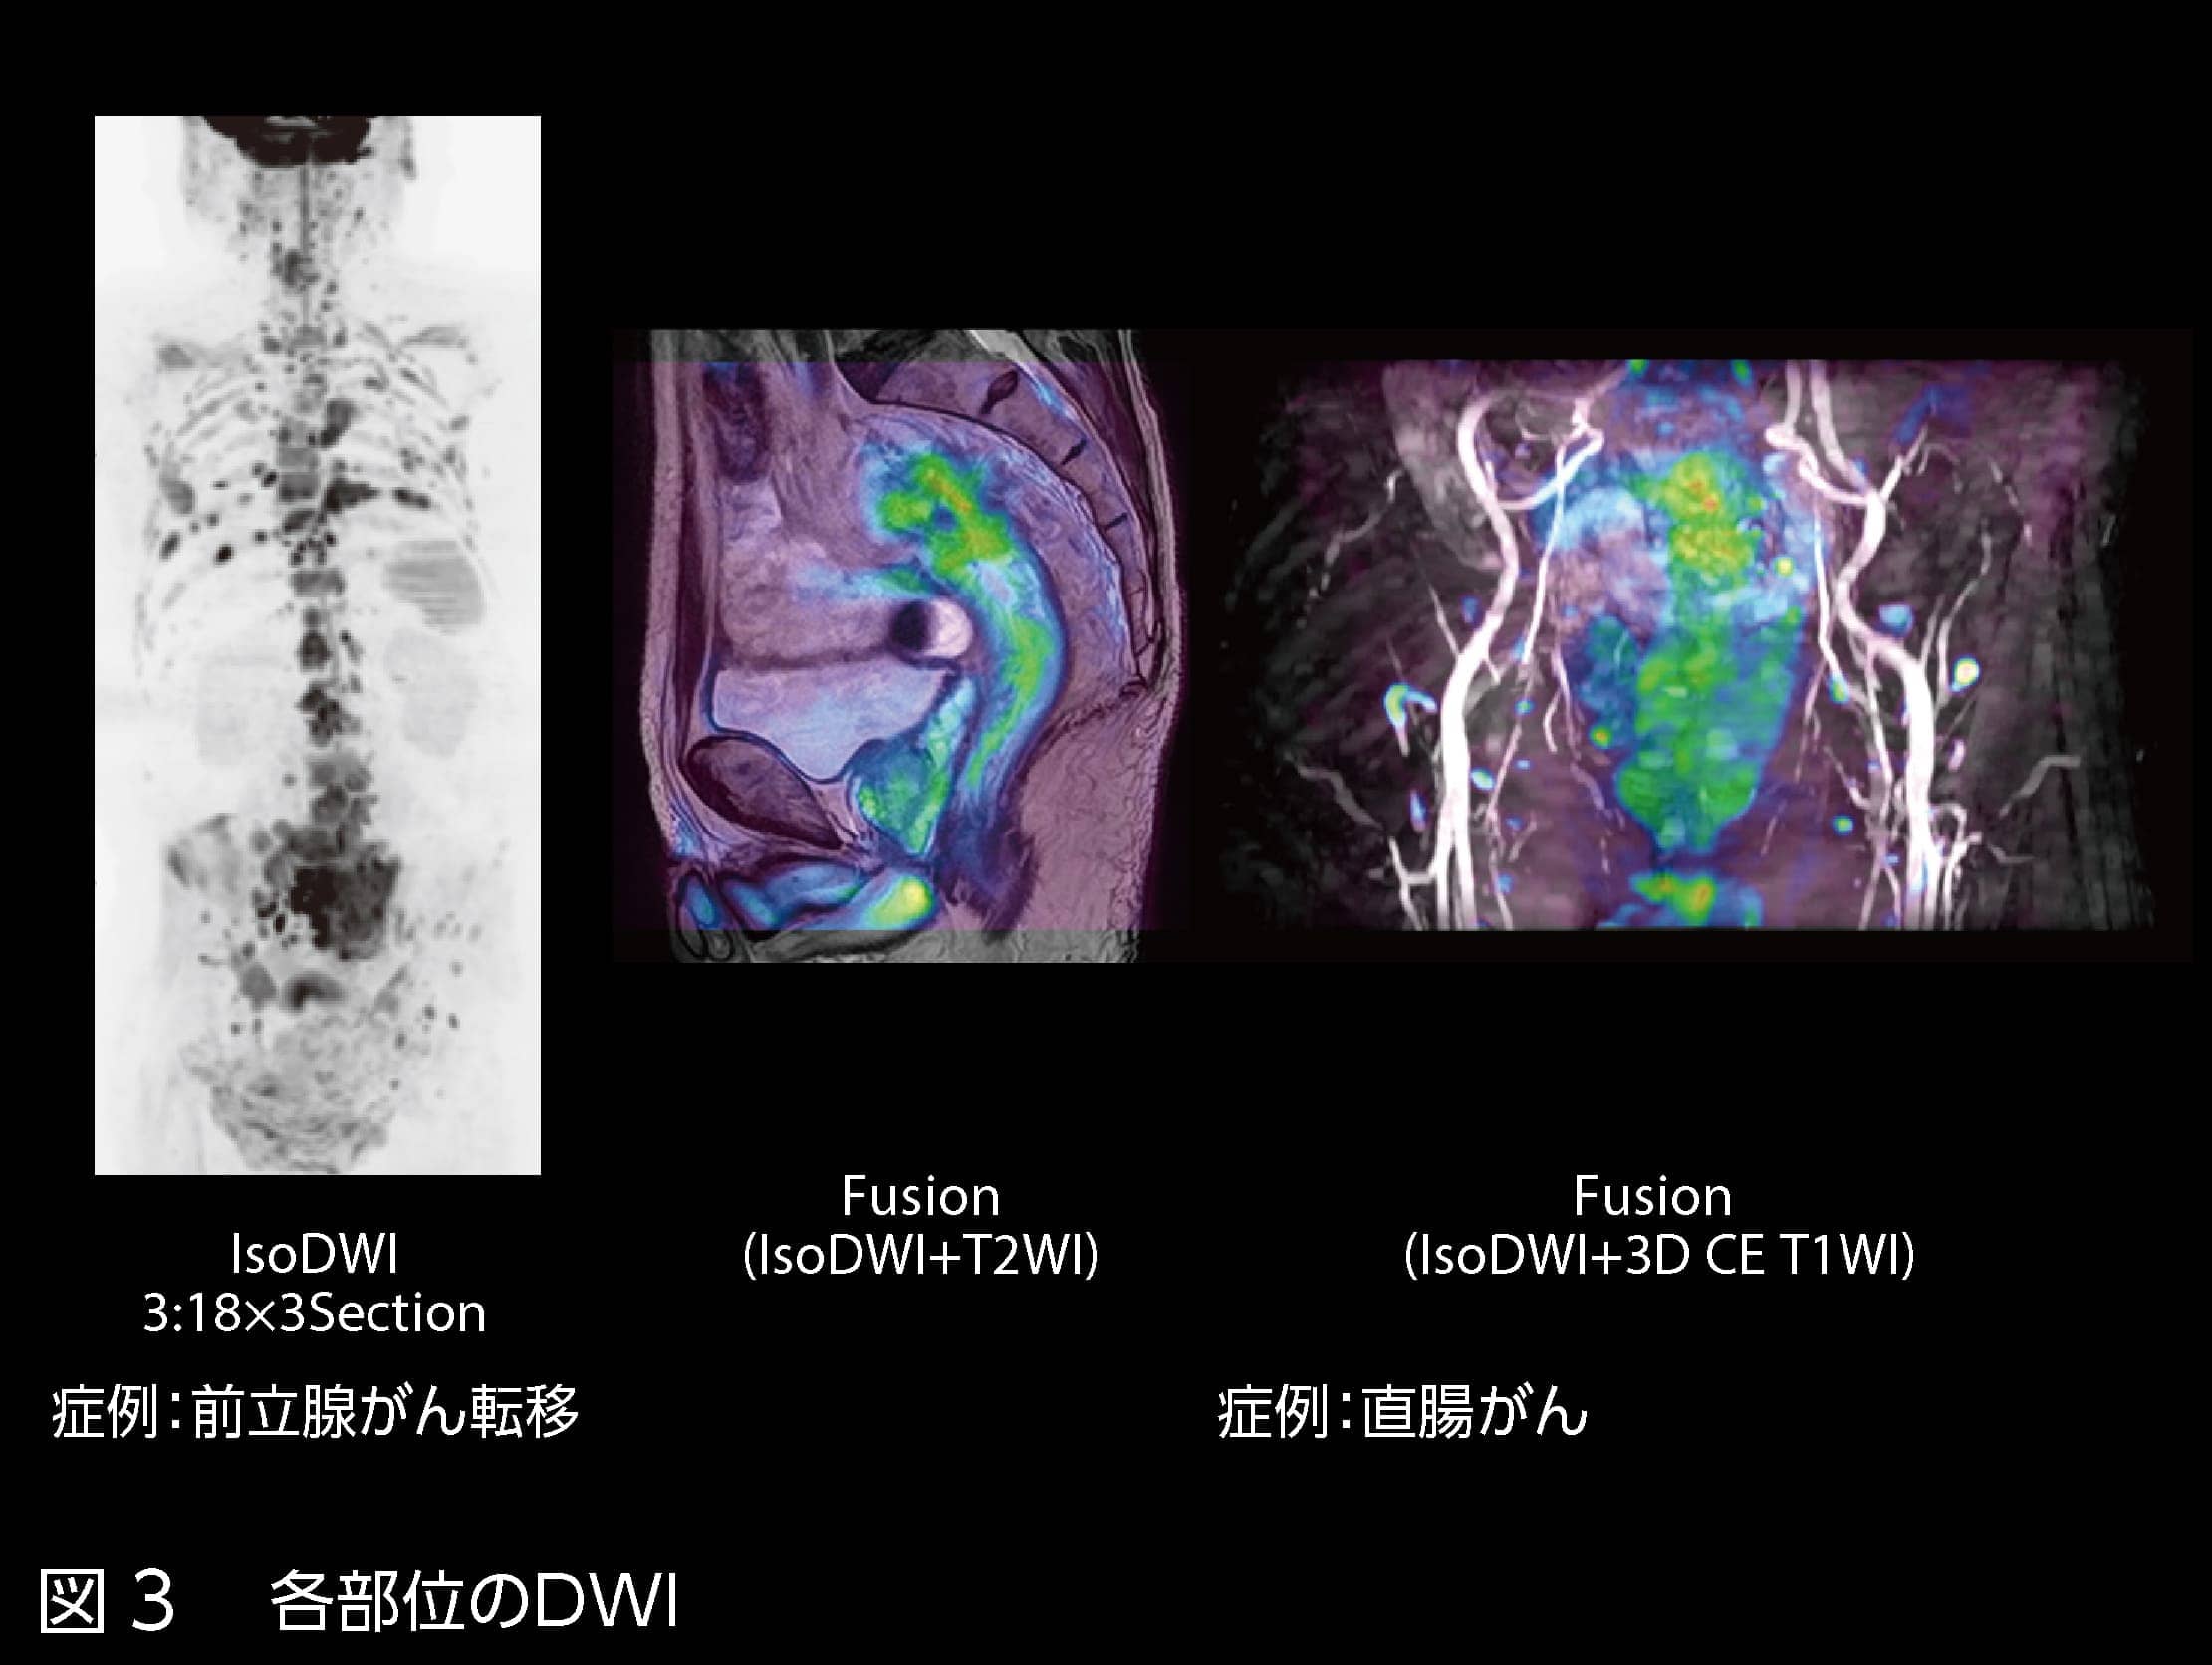

図3 各部位のDWI

― 頭部以外の部位ではいかがですか?

全身DWIでも歪みの少ないDWIが撮像可能です。スティッチングも利便性が高いため、つなぎ目が目立たず歪みの少ない全身DWIを撮像できています(図3)。つなぎ合わせるための苦労がないことは、技師として嬉しいポイントです。

また、コンソール上で簡単にワンクリックで他の画像とカラーフュージョンできる点も重宝しています。DWIは分解能が上げづらいため、分解能の高い画像とフュージョンすることで精度を補うことが可能です。さらに、DWIの歪みが少なく、重なりの精度が高いため、スクリーニングなどに有用だと考えています。